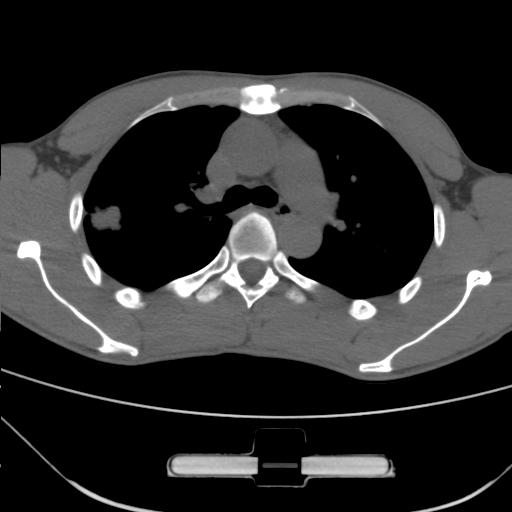

车祸伤者

右肺上叶后段近胸膜下结节样异常密度灶,似见分页及毛刺,考虑右肺上叶周围型肺ca,建议穿刺病理检查

周围型肺ca与炎性假瘤待鉴别。建议穿刺病理检查

考虑周围型肺癌

考虑周围型肺癌可能性大,建议穿刺病理检查

缺乏病史,症状体征,但这个孤立结节具备了几乎所有的恶性征象:分叶,毛刺,空泡征,胸膜凹陷征,血管集束。

考虑右肺上叶后段周围型肺癌。